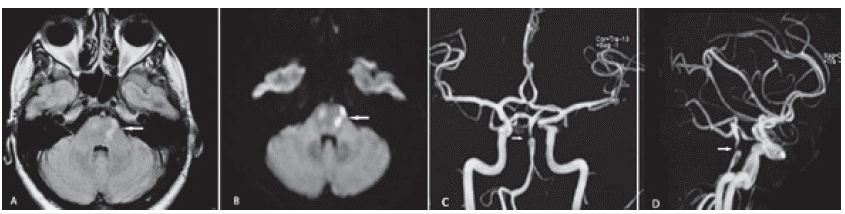

Con el diagnóstico de aneurisma disecante de la arteria basilar y una vez controladas las cifras tensionales, decidimos en conjunto con medicina interna y radiología intervencionista el abordaje de la lesión mediante colocación de dispositivo FRED (Flow-Redirection Endoluminal Device) de 3,5 x 22 mm, en intento de aislar el aneurisma. Se ubicó catéter guía en segmento V2 derecho y se procedió a avanzar microcatéter y microguía. Se logró rebasar distalmente la estenosis, se avanzó y se desplegó satisfactoriamente el dispositivo, de modo que cubrió el segmento estenótico y el cuello del aneurisma. Se verificó permeabilidad de todos los vasos post stent y se observó la exclusión del aneurisma y la permeabilización del vaso afectado (figura 2D), que se ha mantenido como corrobora panangiografía evolutiva luego de un año (figura 3). La paciente inicialmente recibe doble antigaregación con ácido acetil salicílico (ASA) 100 mg/día y clopidogrel 75 mg/día durante seis meses. En la actualidad, ASA 100 mg/día, en seguimiento habitual en la consulta, asintomática en todos los controles.

Panangiografía cerebral evolutiva luego de un año. A. Proyección frontal. B. Vista oblicua. C. Vista lateral izquierda. Se mantiene permeabilidad total de la basilar, conservación de perforantes y aislamiento de la lesión aneurismática (asteriscos).

Figura 3: Panangiografía cerebral evolutiva luego de un año. A. Proyección frontal. B. Vista oblicua. C. Vista lateral izquierda. Se mantiene permeabilidad total de la basilar, conservación de perforantes y aislamiento de la lesión aneurismática (asteriscos).